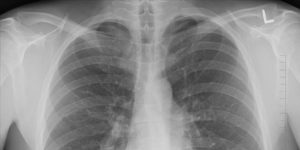

Ex-Smoking COPD Patients Who Switched to Vaping Experienced Long-Term Benefits

Titled “Health effects in COPD smokers who switch to electronic cigarettes: a retrospective-prospective 3-year follow-up”, the earlier study followed 44 patients for a period of three years. The participants were split in two groups, those who switched from smoking to vaping and the ones who kept on smoking. The compiled data indicated that the COPD … Continue reading Ex-Smoking COPD Patients Who Switched to Vaping Experienced Long-Term Benefits